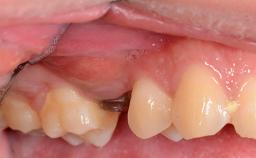

Missing Maxillary Central Incisor, Single Implant Replacement with Adjacent Tooth Restoration

The patient presented with a failing tooth-supported fixed dental prosthesis with cantilever extension replacing the right maxillary central incisor. His chief presenting complaint was poor esthetics, in particular the dark discolored margin around the abutment tooth, the maxillary left central incisor. He reported a history of trauma at a young age, which necessitated the replacement of his maxillary right central incisor as well as root canal therapy of the adjacent left central incisor. The existing prosthesis had been in situ for over 20 years. The initial periapical radiograph displayed good proximal bone levels at the adjacent teeth and a wide incisive canal, which was a concern. The left central incisor presented a very wide root canal treatment with compromised radicular dentin thickness, which was a consideration in the decision between a new tooth-supported fixed dental prosthesis vs. an implant-supported prosthesis. After a lengthy discussion on the risks and benefits of both treatment options, the patient decided on a single-tooth implant replacement.